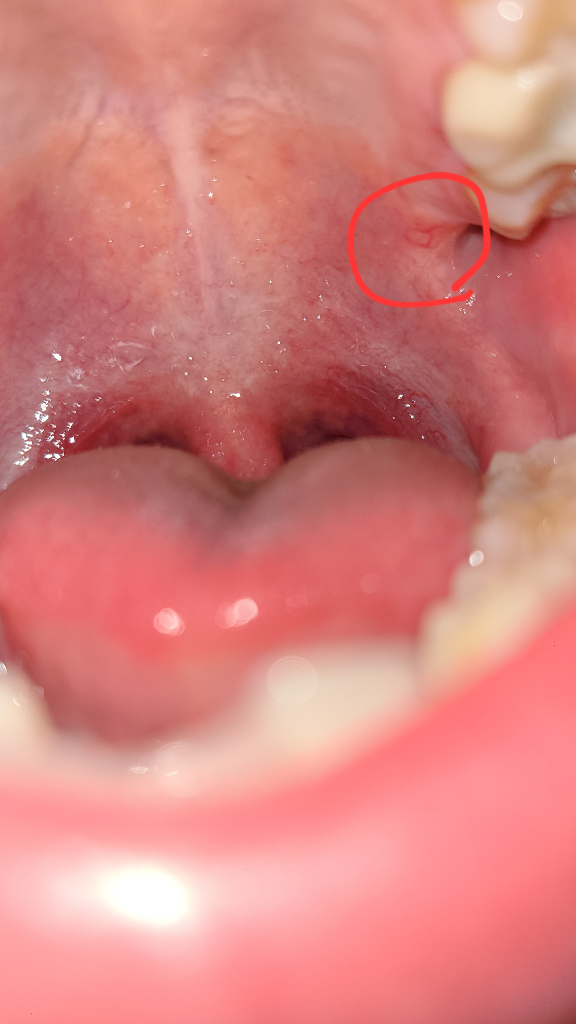

"노란색"으로 표시된 게 "1월 1일"에 찍은 사진이구요

"빨간색"으로 표시된 게 오늘 "1월 12일"에 찍은 사진입니다 현재 재수학원에 다니고 있어서 계속 피곤한 상황이긴 합니다 이번주에 이비인후과에서 탄툼액을 받아서 한 이틀-3일 끊어서 사용했는데도 별다른 차도가 없는 거 같은데 조직검사 받아봐야 하나요?

• 1번 째 사진

• 2번 째 사진